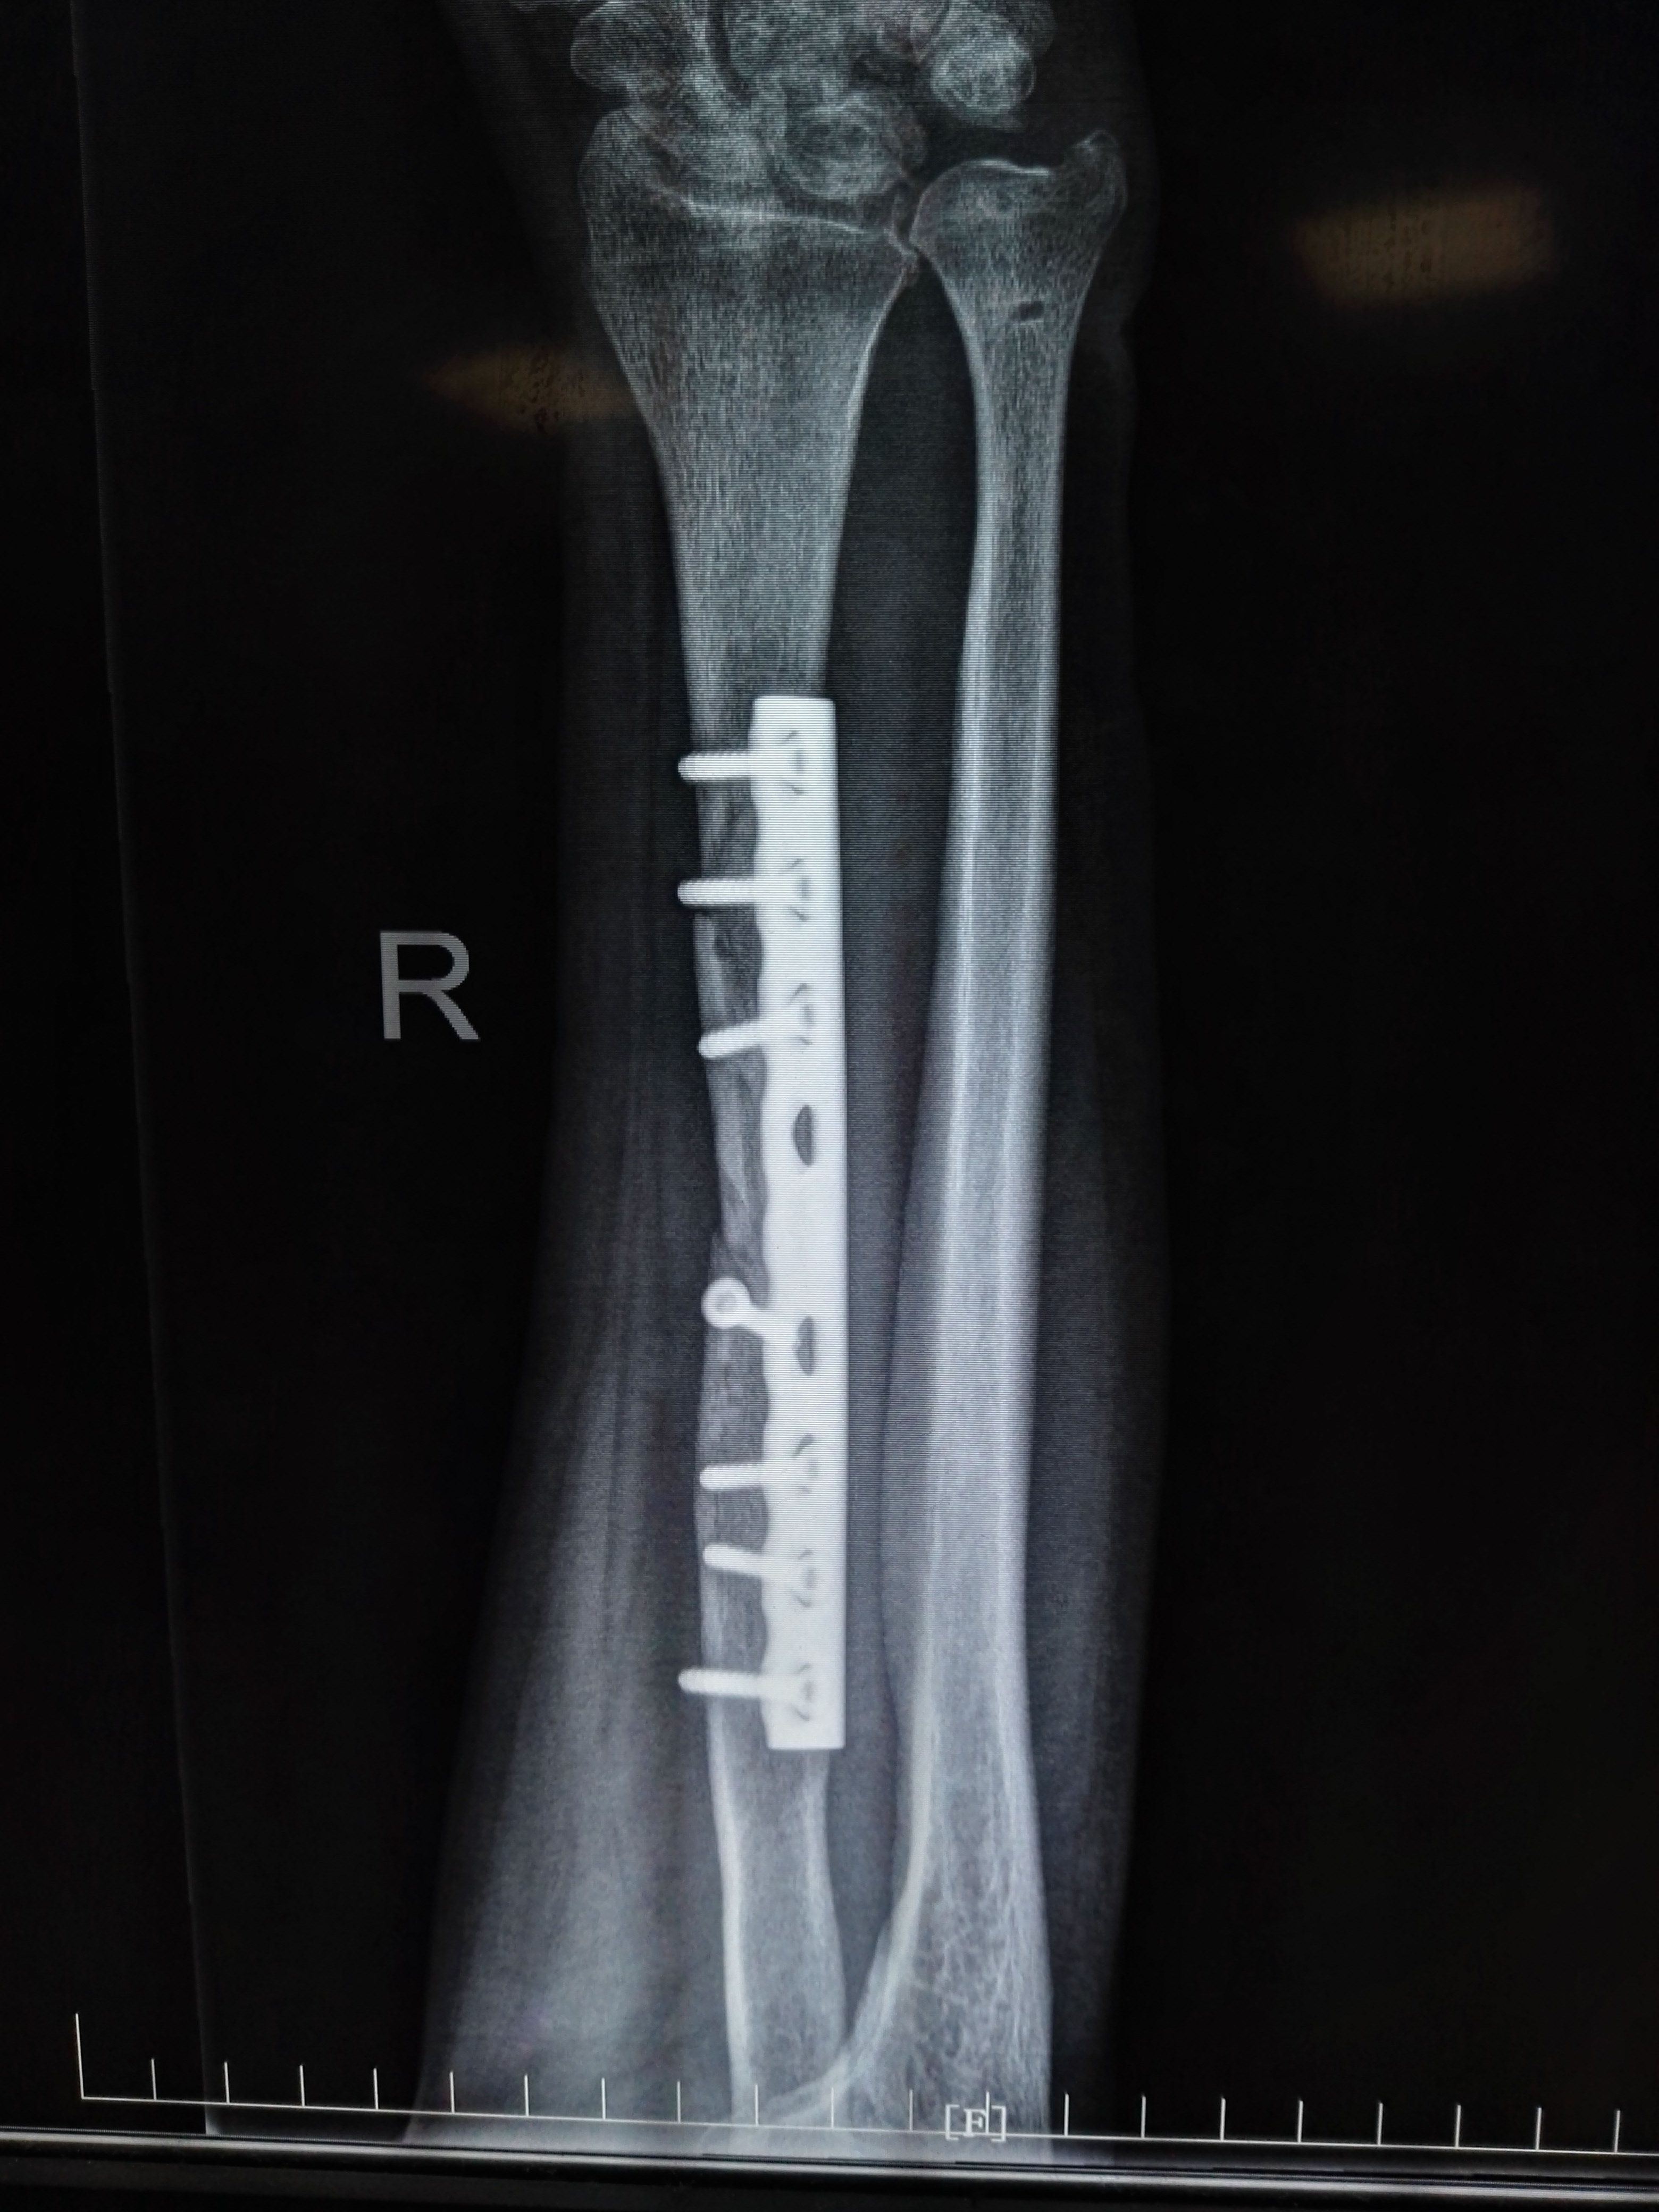

右侧尺骨骨折